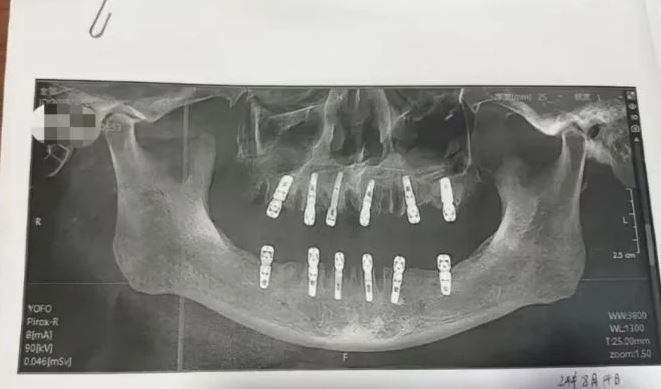

Người phụ nữ này đã đưa ra bằng chứng cho thấy cha cô đã nhổ 23 chiếc răng và trồng 12 chiếc răng mới trong một lần. Cô Shu cho rằng chính điều này là nguyên nhân khiến cha cô tử vong 13 ngày sau đó.

Theo cam kết chấp thuận thực hiện thủ thuật của bệnh nhân, cha của cô Shu thực tế đã nhổ 23 chiếc răng tự nhiên trước khi khoan 12 lỗ vào hộp sọ và xương hàm để trồng những chiếc răng mới. Tất cả những thủ thuật này được thực hiện trong cùng một ngày. Điều đó có nghĩa là ông đã phải chịu đựng cơn đau không thể tưởng tượng được sau khi thuốc gây mê hết tác dụng.

Theo hồ sơ của phòng khám nha khoa Dewei, quy trình nhổ 23 chiếc răng được một bác sĩ tên Yuan thực hiện. Người này có chuyên môn bao gồm điều trị tủy, nhổ răng khôn mọc ngầm và răng giả toàn phần. Mặc dù hiện tại không có quy định cụ thể nào về số lượng răng được nhổ trong một lần, nhưng phòng khám và bác sĩ phải cân nhắc đến khả năng chịu đau của bệnh nhân và nguy cơ nhiễm trùng.